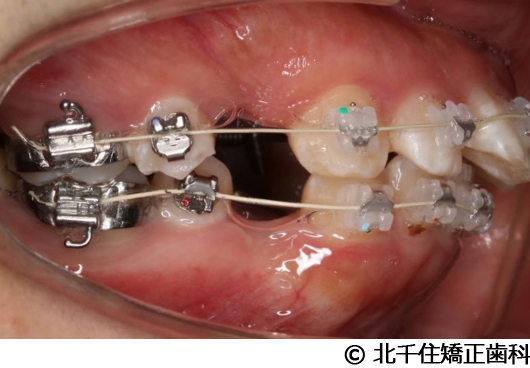

- 治療中

顎関節症(非復位性顎関節円板障害)、スタビライゼーションスプリントにより顎関節の安定化を図り、上下顎小臼歯4本を抜歯して矯正用アンカースクリューを併用してワイヤー矯正治療(セラミックブラケット)。

スプリント療法後に顎位の安定化を図り、矯正治療により歯列および咬合関係の調整を行った症例である。現在は保定装置を使用し、歯列および咬合の安定維持のため定期的な経過観察を行っている。